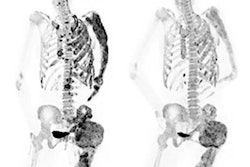

Deep learning can classify bone lesions found on F-18 sodium fluoride (NaF) PET/CT exams, potentially enabling monitoring of individual lesions and faster interpretation times, according to research presented recently at the Society of Nuclear Medicine and Molecular Imaging (SNMMI) annual meeting in Philadelphia.

F-18 NaF PET is used to identify bone metastases, which are very common in many cancers -- especially prostate cancer, according to Bradshaw. The uptake of F-18 on PET is a result of the bone remodeling that occurs during metastasis.

However, NaF-PET also produces false positives from, for example, degenerative joint disease, which causes F-18 to be taken up by the bone and presents a similar appearance to metastatic disease. This reduces NaF-PET's specificity, a limitation that is exacerbated by the fact that patients with bone metastases can have dozens or even hundreds of lesions, Bradshaw said.